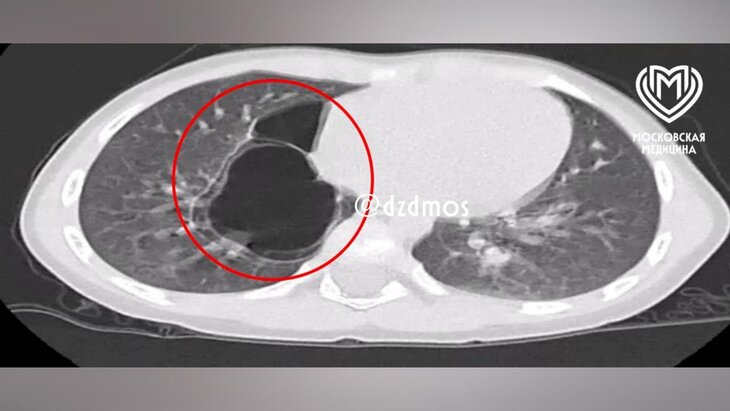

Фото: телеграм-канал "Московская медицина"

Рентген выявил уплотнения в правом легком, а компьютерная томография позволила установить точный диагноз – врожденную кистозно-аденоматозную мальформацию легких.

При таком нарушении здоровая легочная ткань замещается аномальной, что приводит к образованию кист. Со временем они увеличиваются и могут вызывать дыхательную недостаточность и тяжелые воспалительные осложнения.

Как пояснил детский хирург отделения № 2 Ампар Фатима, с помощью специального инструмента были извлечены два тонкостенных кистозных образования диаметром до 6 и 3 сантиметров, внутри которых находились дополнительные мелкие кисты.